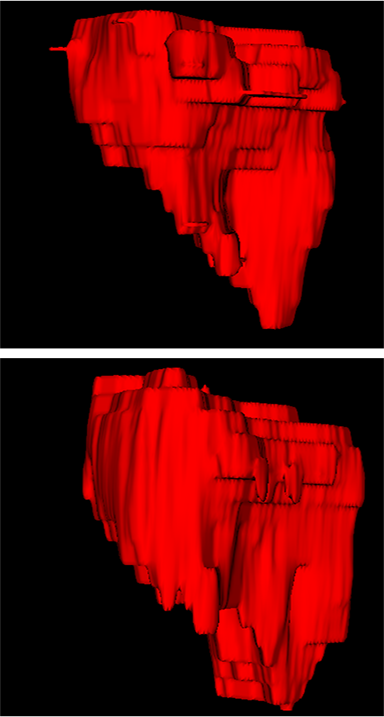

Comparison with ground truth. Some predicted results of MMFNet are shown in 2D images and 3D images in Figure 7 and Figure 8. As shown in these figures, although the shape and size of NPC are varied from each other, MMFNet can still accurately determine the regions of NPC and obtain the accurate contours of tumors. Through analyzing 2D images in figure 7, MMFNet has a capacity to fuse multi-modality MRI to reduce the confusion brought by intensity’ similarity between nearby tissues and NPC. The values of , and of MMFNet are shown in Table 1. MMFNet can reach the best results with , and .

Comparison with related works. Table 1 reports the values of , and for different methods. Predicted masks of different methods are illustrated in Figure 9 and Figure 10, which respectively present results in 2D and 3D images. Through comprehensively analyzing these results, the proposed MMFNet actually have the following properties:

(i) It directly fuses 3D MRI images rather than 2D slices. Thus, it can effectively use meaningful information from neighboring slices of MRI to realize NPC segmentation. As shown in Table 2, MMFNet can bring , and improvements in and compared to the best method based on 2D images (Multi-modality patch-based CNN). And Figure 10 shows that 3D-based methods have less isolated regions (false positives) than 2D-based ones.